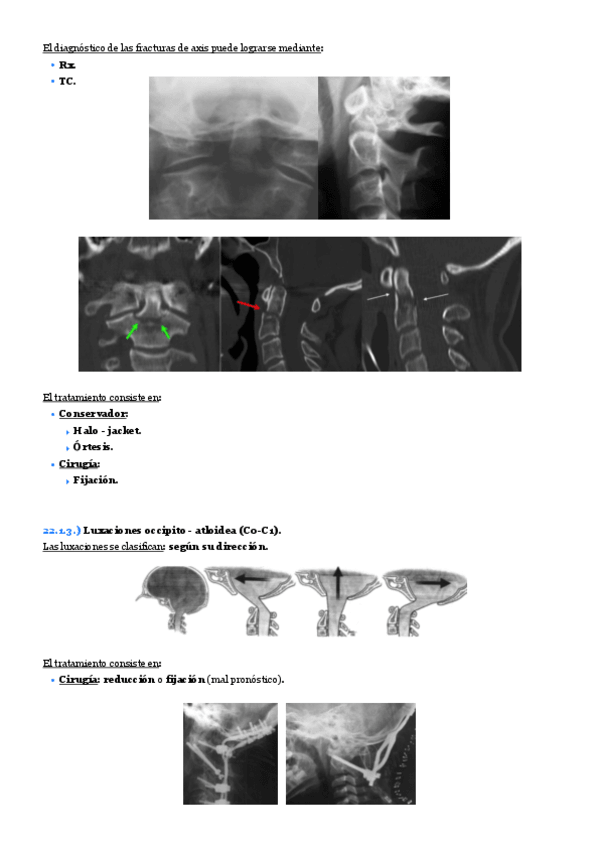

He publicado nuevos apuntes de 2º Patologia Médica y Farmacología I: Tema-22.-Lesiones-traumaticas-de-la-columna-cervical..pdf